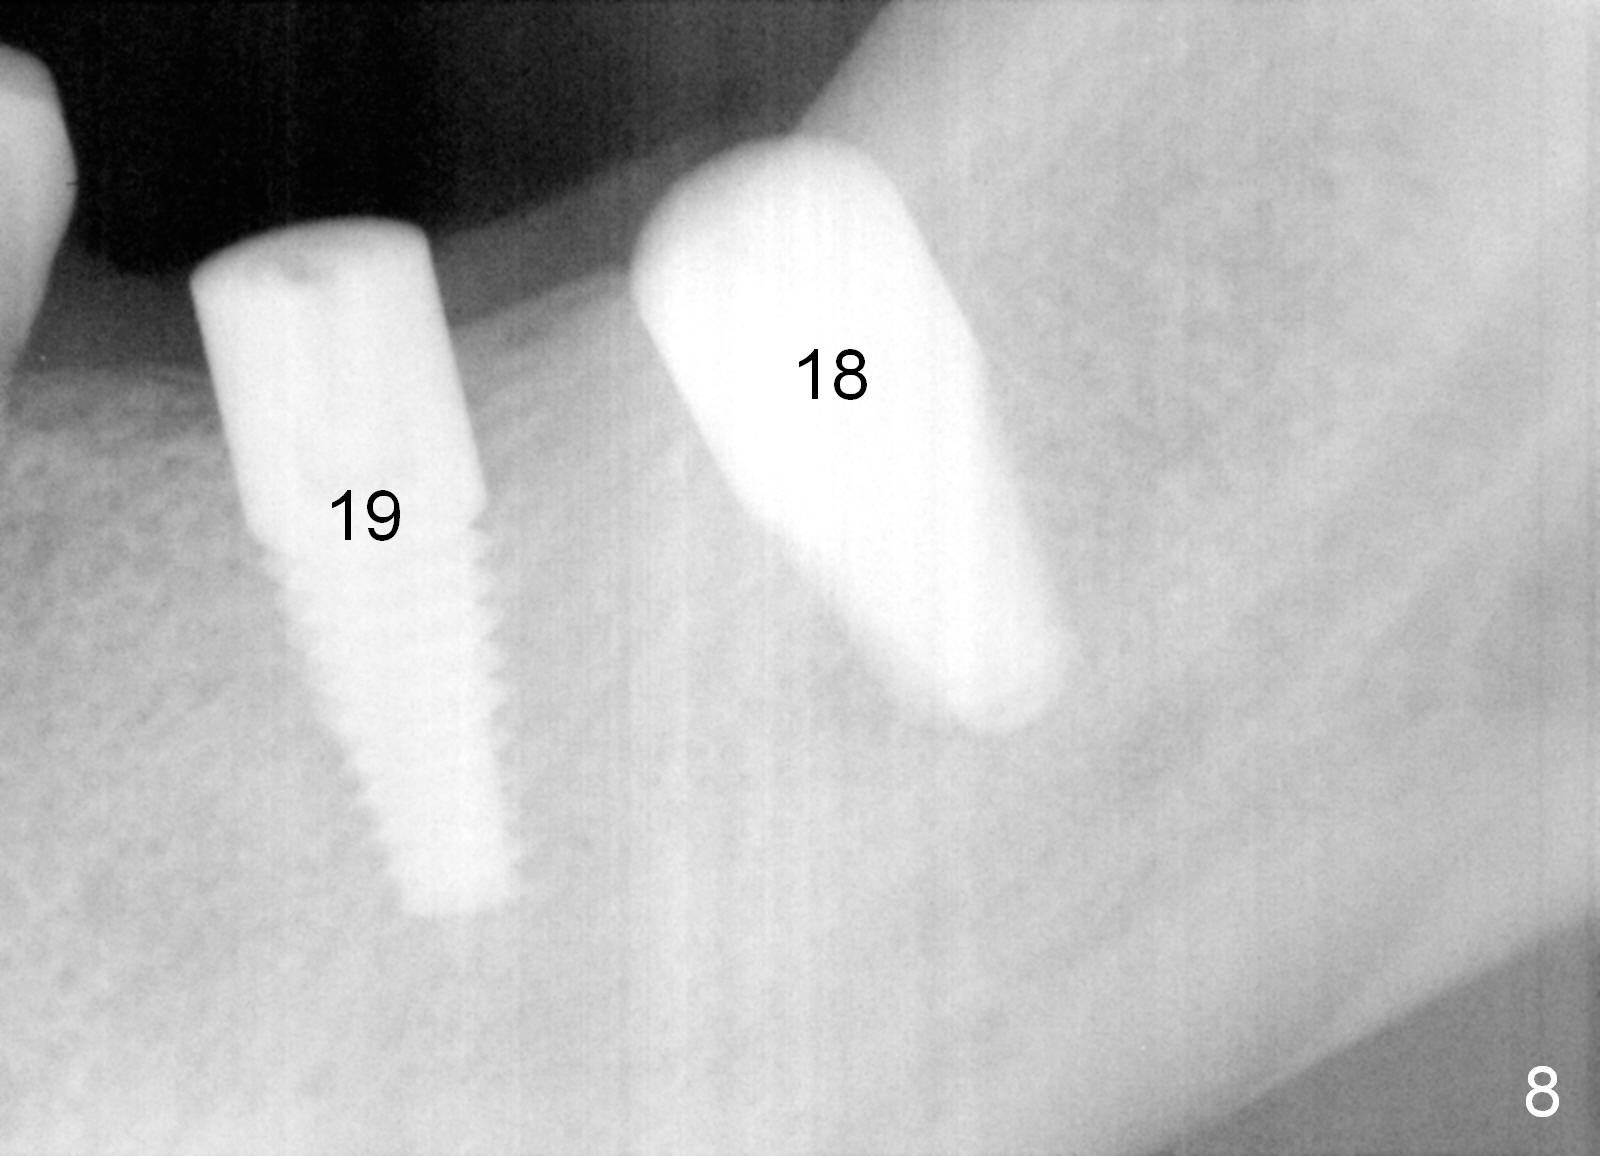

There is no bone loss around the implants 3 months postop (Fig.8). Crowns are delivered 5 months postop and have been in function for 3 months now. There is no gingival recession around the crowns. Panoramic X-ray is taken 1.5 years postop (1 year 1 month post cementation, Fig.9); there is mild bone resorption distal to #19 implant (*).